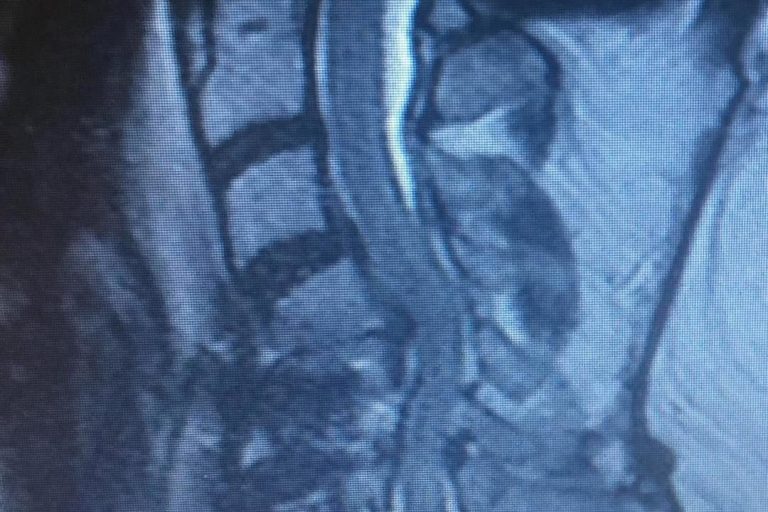

Meet Lin Sanders—a true inspiration of resilience and determination! Part 1 Lin underwent a complex two-level lumbar fusion at Texas Neuro-Spine Surgery. The procedure involved an anterior lumbar interbody fusion (ALIF) at L3-4 and L4-5, followed by laminectomies and pedicle screw instrumentation at the same levels. These surgeries were performed to help address her back…